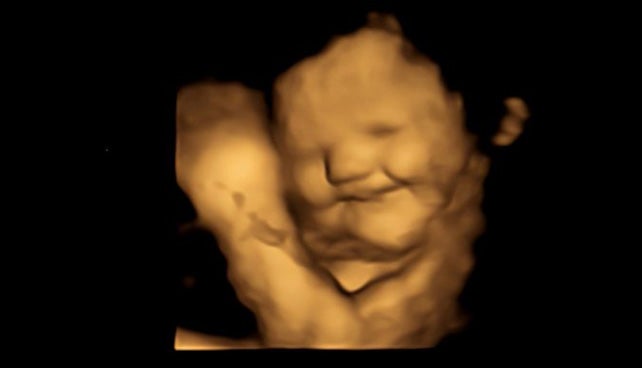

Cuenta el equipo que los hallazgos son la primera evidencia directa de que los bebés reaccionan de manera diferente a varios olores y sabores antes de nacer. Para ello, examinaron ecografías 4D de 100 mujeres embarazadas y descubrieron que los bebés expuestos a sabores de zanahoria mostraban respuestas de “cara de risa”. Por contra, aquellos expuestos a sabores de col rizada mostraron más respuestas de “llanto”.